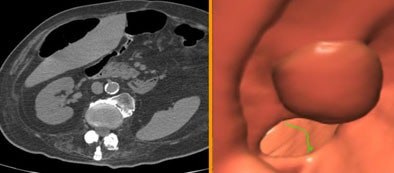

![]() |

| In a 72-year-old screening patient with severe diverticular disease, the colonoscope had stopped at the sigmoid colon. VC results showed the colon to be free of disease, but detected a very large extracolonic mass, diagnosed as a peritoneal liposarcoma. |